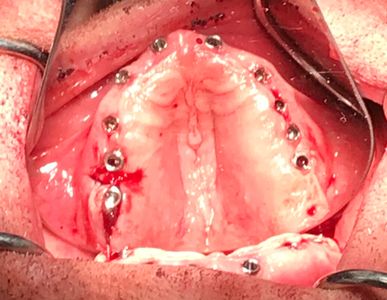

The upper implants have all been placed. Now surgery will begin on the lower arch.

Surgery on the top and bottom is done! Louis has 19 implants now; 10 on top and 9 on the bottom. Surgery lasted for approximately 2 1/2 hours.